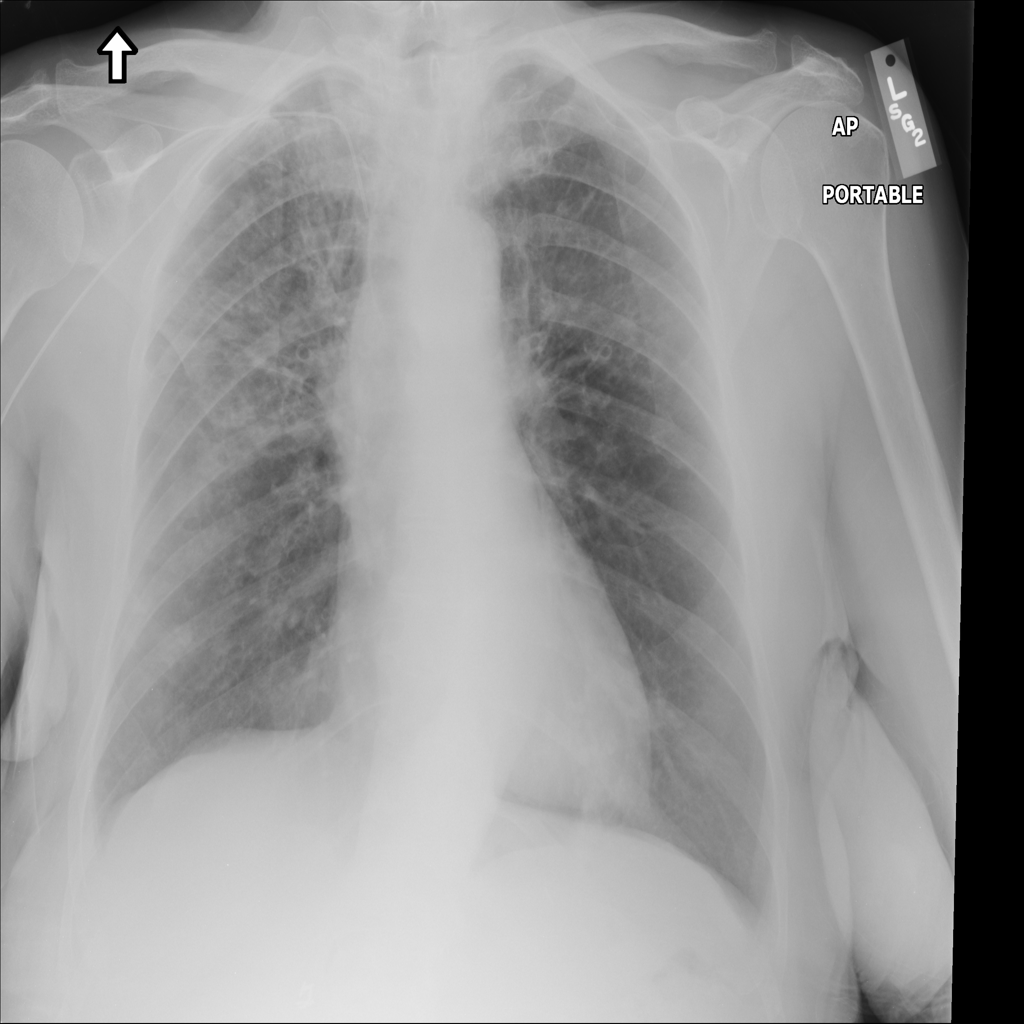

Showing up to 90 reference images for Nodule.

PAT-988D · IMG-001Nodule

PAT-988D · IMG-001

AP